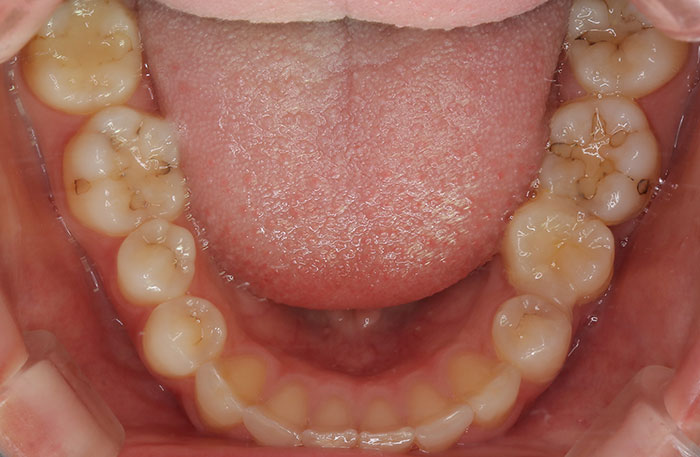

親知らずの歯を移植したケースです。患者様はとても喜ばれておりました。